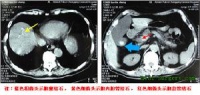

大多起病缓慢,迷走神经切断术者常于术后第2周开始进流质饮食后发病。主要症状有腹胀、上腹或脐周隐痛,恶心和持续性呕吐。呕吐物为混浊的棕绿色或咖啡色液体,呕吐后症状并不减轻。随着病情的加重,全身情况进行性恶化,严重者可出现脱水、碱中毒,并表现为烦躁不安呼吸急促、手足抽搐血压下降和休克。突出的体征为上腹膨胀,可见毫无蠕动的胃轮廓,局部有压痛叩诊过度回响,有振水声。脐右偏上出现局限性包块,外观隆起,触之光滑而有弹性、轻压痛,其右下边界较清,此为极度扩张的胃窦,称“巨胃窦症”,乃是急性胃扩张特有的重要体征,可作为临床诊断的有力佐证。

实验室检查可发现血液浓缩、低血钾、低血氯和碱中毒。立位腹部X线片可见左上腹巨大液平面和充满腹腔的特大胃影及左膈肌抬高.